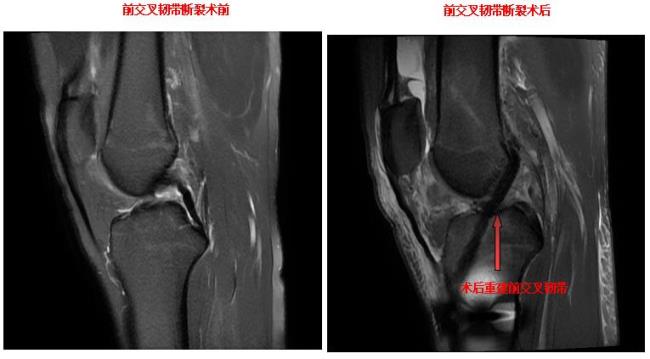

经关节镜微创交叉韧带重建

关节镜下前交叉韧带下止点撕脱骨折复位固定